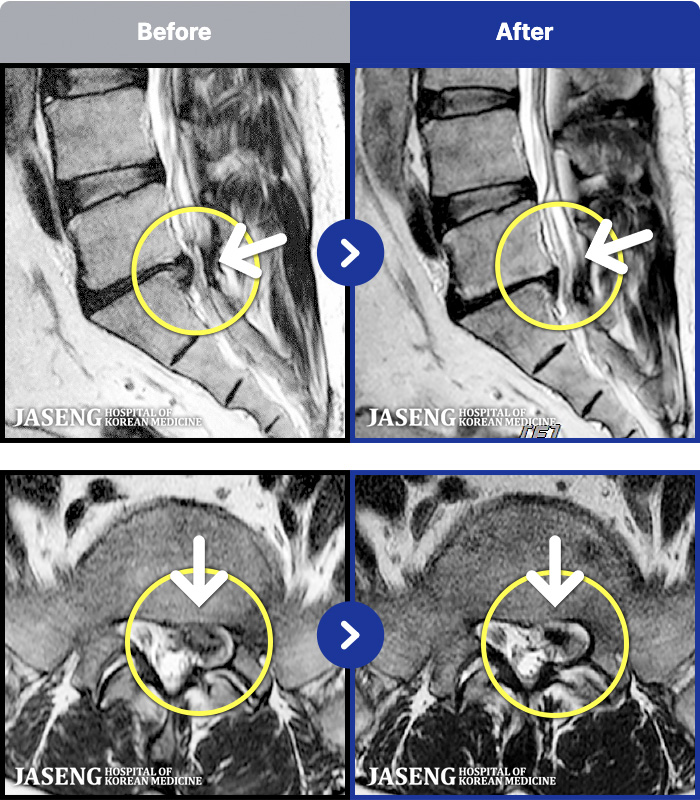

MRI ġ

MRI ũ ʸ Ȯϼ.